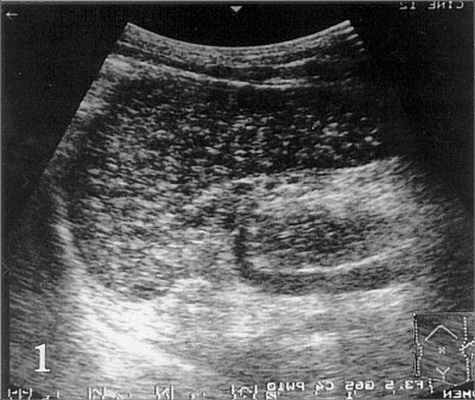

Рис. 1. На эхограмме селезенки больного циррозом печени и портальной гипертензией определяются мелкие диффузные гиперэхогенные включения (точечные кальцификаты).

На эхограмме в левой косой проекции (рис. 1) визуализируются диффузные гиперэхогенные включения (точечные кальцификаты) в селезенке, состоящие из телец Гамна-Гэнди. При сканировании в правом подреберье (рис 2b) визиализируется печень повышенной эхогенности, с неоднородной структурой, образованием узлов в ее паранхиме и расширением пупочной вены.

Тельца Гамна-Гэнди представляют собой ограниченные организованные кровоизлияния в селезенке, вызванные портальной гипертензией. Тельца Гамна-Гэнди состоят из фиброзной ткани, гемосидерина и кальция.

Они обычно расположены в перифолликулярной и трабекулярной зоне и состоят из фиброзной ткани, с вкраплениями гемосидерина и кальция. Yasuhara с соавторами при проведении УЗ-исследования определяли тельца Гамна-Гэнди в виде диффузных гиперэхогенных включений, подобные повреждения они обнаружили на аутопсии у 12,9% больных циррозом печени. Изучив корреляцию морфологических и эхографических признаков, авторы пришли к выводу, что эхография позволяет увидеть в селезенке тельца Гамна-Гэнди диаметром больше 1 мм и широко распространенные. Тельца Гамна-Гэнди определяются при портальной гипертензии, синдроме Банти, наследственном сфероцитозе, застойной сердечной недостаточности, внутрибрюшинном воспалении или при прорастании воротной вены карциномой желудка либо карциномой поджелудочной железы. Тяжелые хронические заболевания и их осложнения могут вызывать образование расссеянных кальцифицированных очагов. Наиболее частой причиной является туберкулез. Рассеянные кальцификаты возникают также при длительно текущем гистоплазмозе или токсоплазмозе. При цистицеркозе они обнаруживаются значительно реже. Длительно существующая застойная селезенка вызывает значительное увеличение органа. Селезенка становится плотной, и плотность ее увеличивается по мере нарастания застойных явлении. Капсула селезенки становится утолщенной и фиброзированной, но не вовлекается в процесс. На срезе ткань селезенки напоминает мясо, цвет ее варьирует от серо-красного до темно-красного, в зависимости от степени фиброза. Часто мальпигиевы тельца не видны. Небольшие серо-коричневые плотные узлы, рассеянные в красной пульпе селезенки, составляют так называемые тельца Гамна-Гэнди.